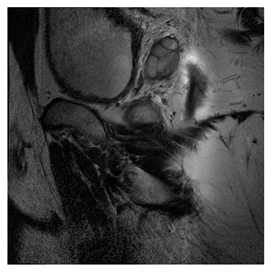

Breast-MRI-NACT-Pilot is an MRI-type image database, collecting breast medical images of 64 patients. Some samples are shown in Figure 12a.

Figure 12.

Sampled images in the tested benchmark databases: (a) Breast-MRI-NACT-Pilot (breast), (b) ACRIN-DSC-MR-Brain (brain), (c) NIH (chest), (d) Lung-PET-CT-Dx (lung), (e) Prostate-MRI (prostate), and (f) Other grayscale standard images.

- Prostate-MRI Database (available at: https://wiki.cancerimagingarchive.net/display/Public/PROSTATE-MRI (accessed on 4 November 2021))

Prostate-MRI database contains MRI-type medical images and collects prostate medical images. Some samples are shown in Figure 12e.

In this subsection, we describe three experiments used to measure the performance of the proposed method. The first experiment shows the stegoimage and marks the pixels’ positions that have been modified during the embedding process, as shown in Table 2, Table 3, Table 4, Table 5, Table 6 and Table 7. To make modified pixel positions have a pronounced effect, we set bpp (bit per pixel) rate at 0.05 and 0.025. It can be seen from the results that the proposed local complexity function can distinguish ROI and RONI from most of the medical images, so modified pixels are mainly gathered in RONI. However, it is observed that the proposed local complexity function cannot distinguish between ROI and RONI in the Prostate-MRI database due to the relative complexity of the image. Besides, “Modified BPP” represents the proportion of pixels in the image that have been modified. We observed that the performance of “baboon” in the grayscale standard images database is poor because that image’s pixels are relatively complex. It becomes challenging to select the more embeddable pixels based on the proposed local complexity function. Nevertheless, the modified pixel positions in other grayscale standard images, such as Lena and Barbara, are relatively smooth, verifying that our local complexity function is also applicable to general images.